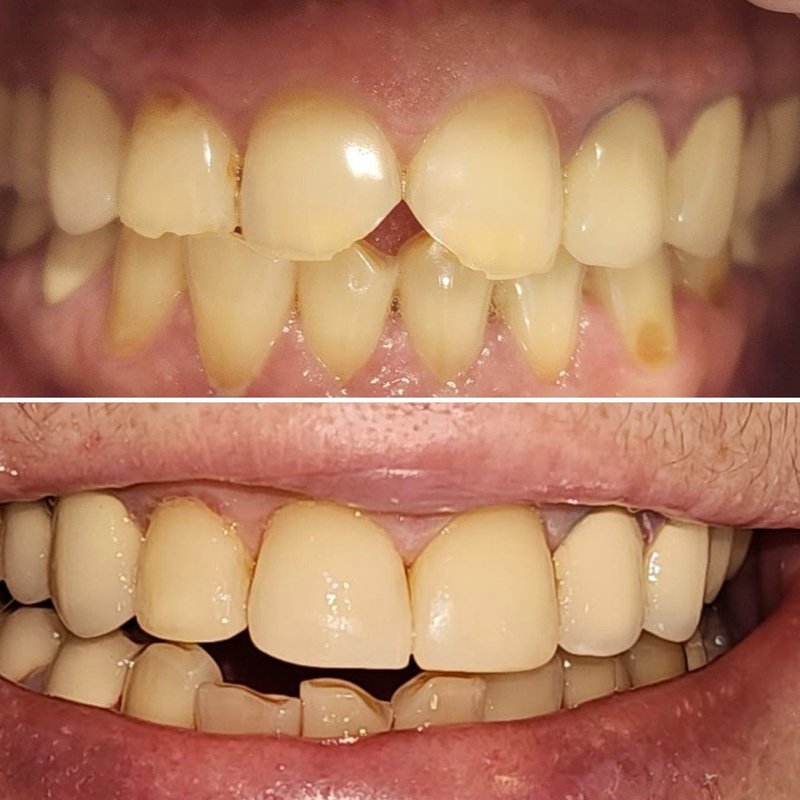

Фотогалерея